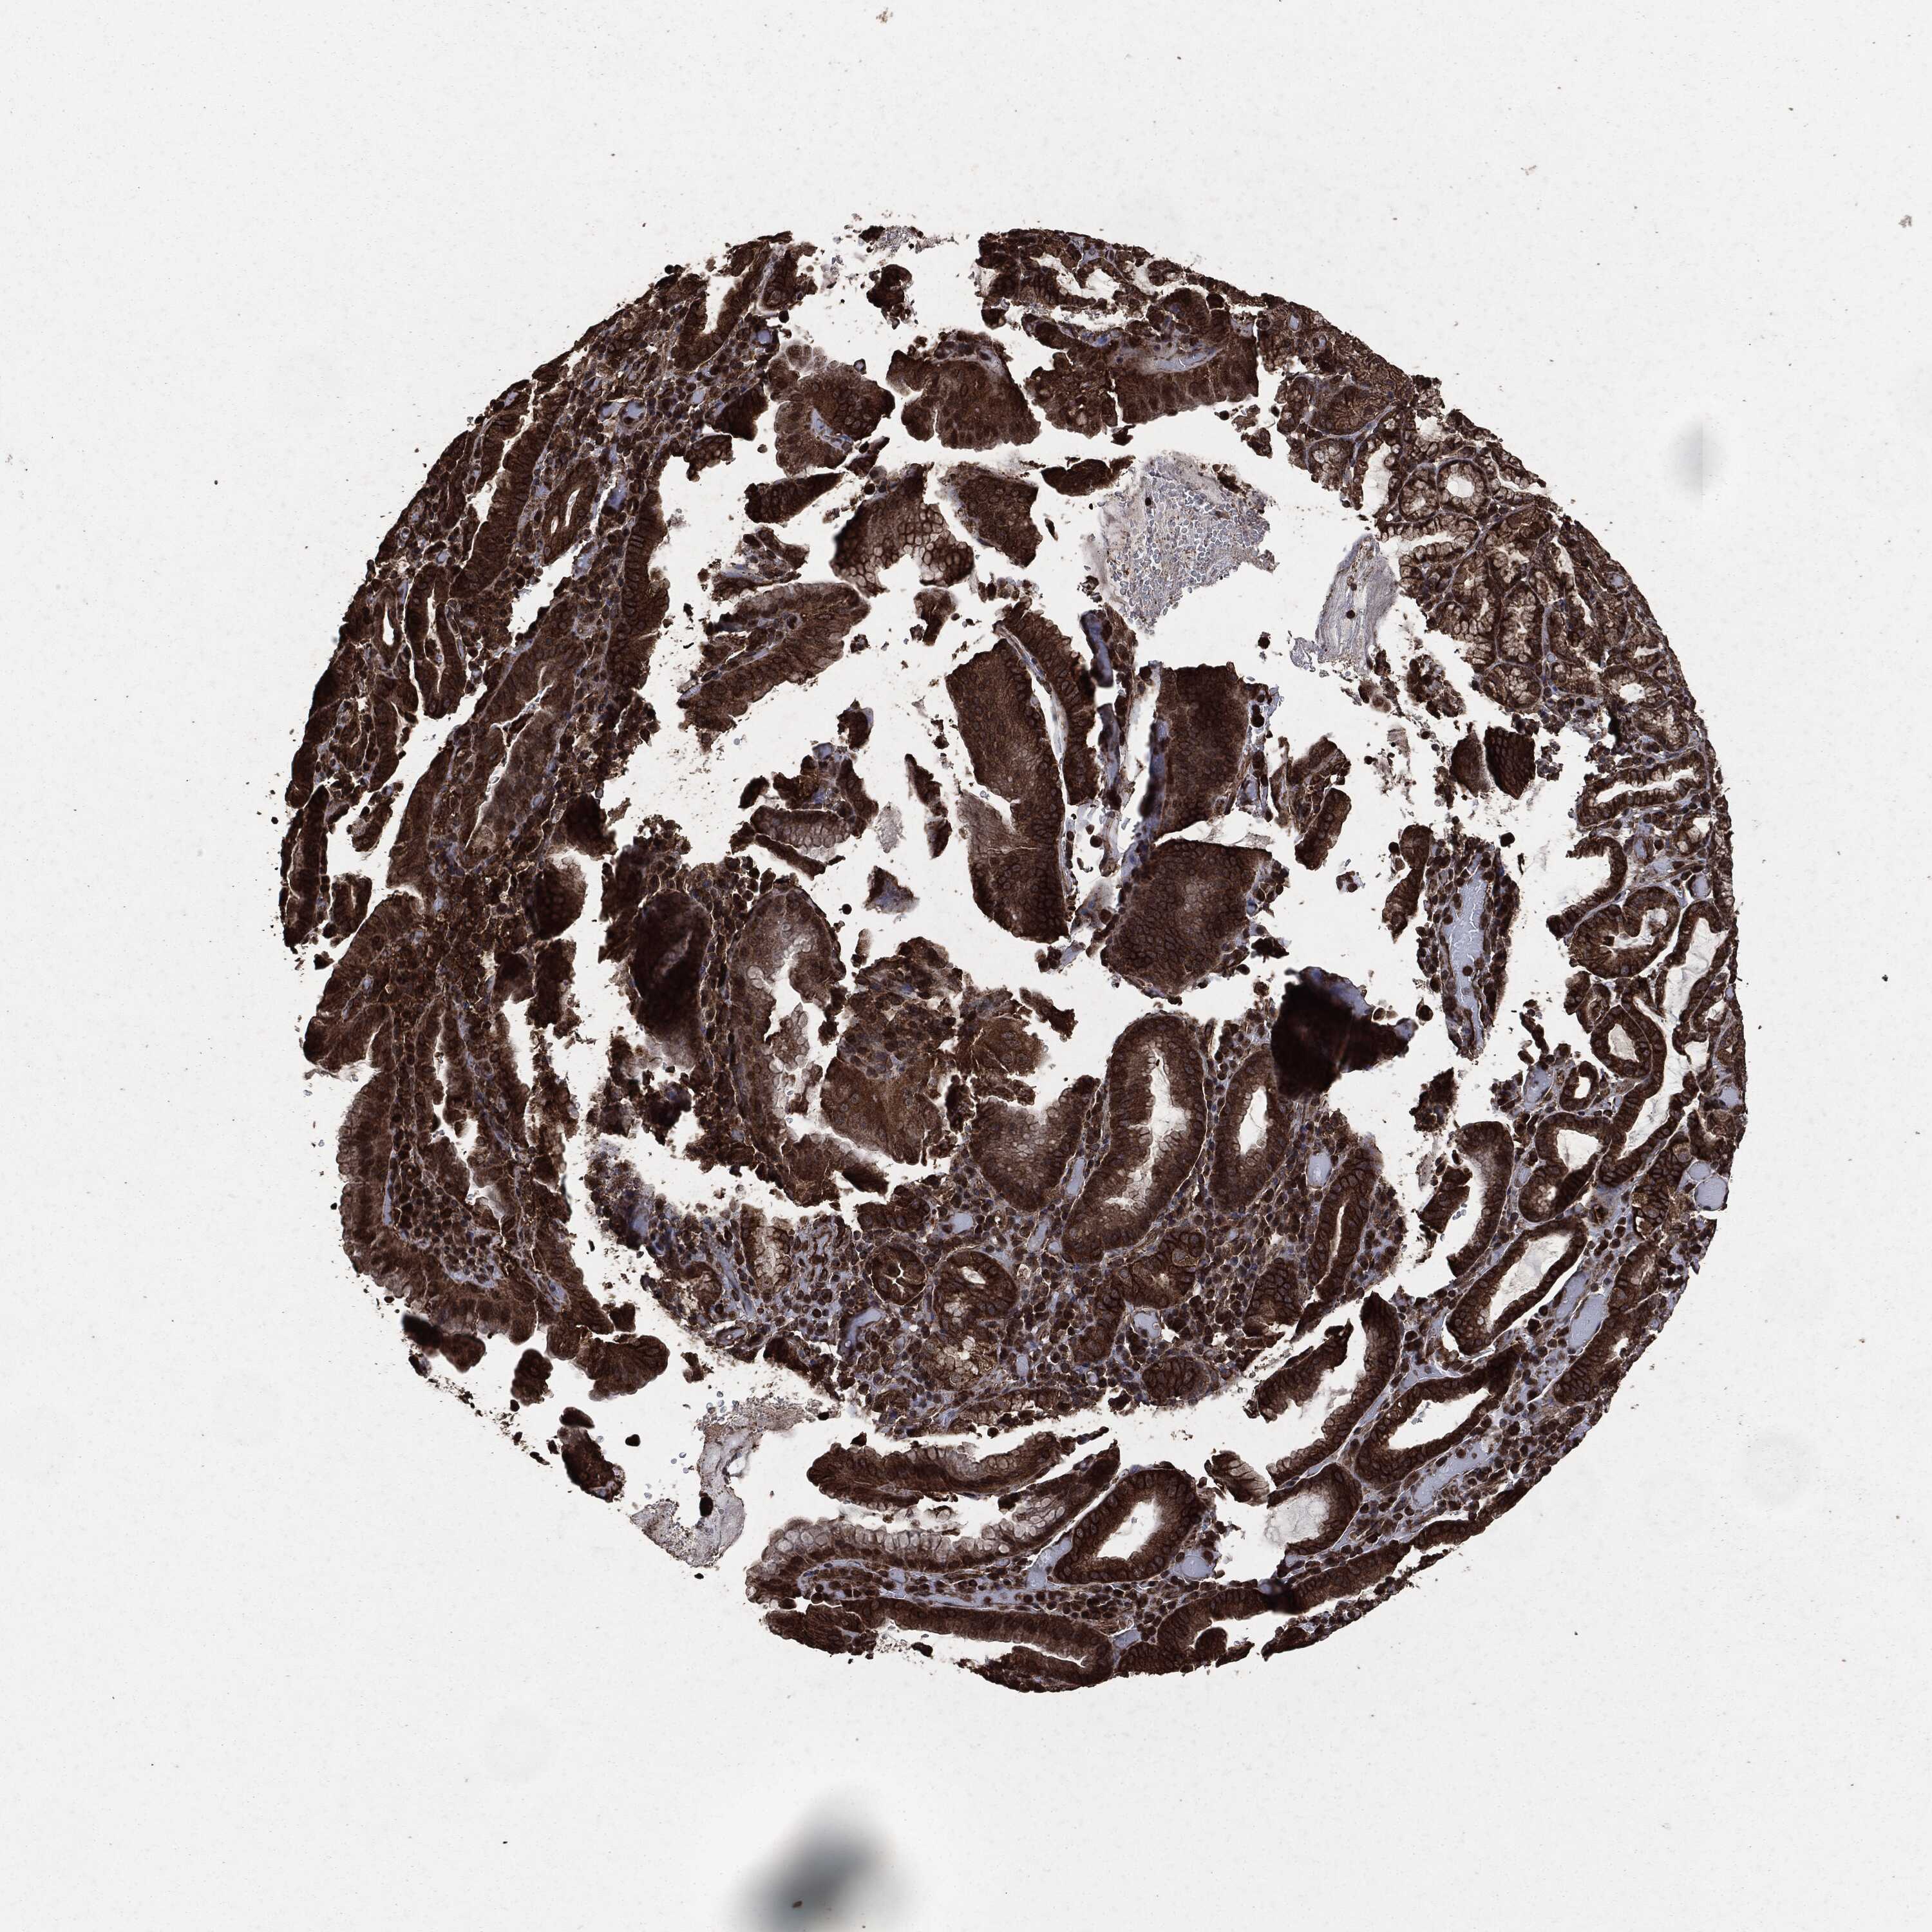

STOMACH CANCER - Protein expressioni

A mouse-over function shows sample information and annotation data. Click on an image to view it in a full screen mode. Samples can be filtered based on level of antibody staining by selecting one or several of the following categories: high, medium, low and not detected. The assay and annotation is described here.

Note that samples used for immunohistochemistry by the Human Protein Atlas do not correspond to samples in the TCGA dataset.

Antibody stainingi

Antibody staining in the annotated cell types in the current human tissue is reported as not detected, low, medium, or high, based on conventional immunohistochemistry profiling in selected tissues. This score is based on the combination of the staining intensity and fraction of stained cells.

Each image is clickable and will lead to virtual microscopy that enables deeper exploration of all samples and also displays staining intensity scores, fraction scores and subcellular localization as well as patient and tissue information for each sample.

HPA049830

CAB002015

CAB080330

CAB080331

CAB080332

Staining

High

Medium

Low

Not detected

Intensity

Strong

Moderate

Weak

Negative

Quantity

>75%

75%-25%

<25%

None

Location

Nuclear

Cytoplasmic/membranous

Cytoplasmic/membranous,nuclear

Adenocarcinoma, NOS

Adenocarcinoma, High grade